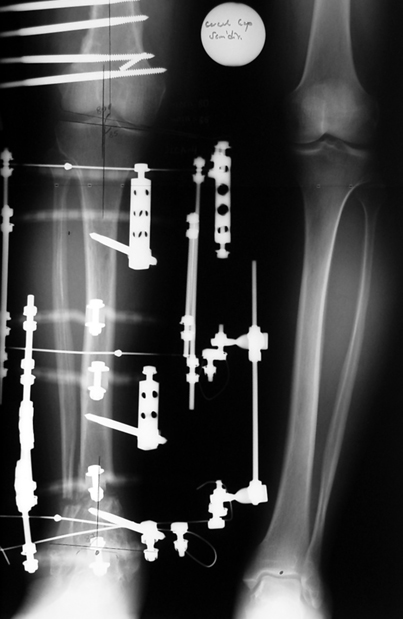

Kırık kaynama yokluklannın tedavisi hala, ortopedik cerrah için çözümü güç sorunlardandır. Tek bir tedavi yöntemi yoktur. Tüm bu yöntemler problemli ve daima komplikasyonlara açıktır. Kaynamamaya enfeksiyon, yumuşak doku kaybı ile deformite ve kısalık eşlik edebilmektedir, Kaynamama için internal ve eksternal birçok teknik belirtilmiştir. Kaynamayan kemik uçlarının çıkartılması, damarlı fibula veya fibula grefti, damarlı kas greftleri ile birlikte internal fiksasyon uygulamaları, elektrik stimulasyon gibi uygulamalar kaynamamada bir şeçenektir. Fakat kısalık ve deformite gibi ek patolojiler tedavisinde kısıtlı kalmaktadır. İlizarov eksternal fiksatörü ile uygulanan distraksiyon osteogenezi uygulamaları ile birlikte yapılan psödoartroz sahasından akut kısatma ve aynı kemikteki diğer segmentten uzatma yapılmaktadır. Ilizarov ve arkadasları, kendi geliştirdikleri yöntem ve fiksatörle, aynı anda, hastanın günlük aktivitelerini kısıtlamadan, eklem fonksiyonlarını koruyarak kaynamayı basarmıs,deformiteyi düzeltmis, uzunlugu yeniden sağlamıstır. Bu teknik sayesinde kemik defektlerinin kapatılması ve enfeksiyon gibi hastaya morbidite getiren ek patolojiler giderilmiş aynı zamanda kısalıkta telafi edilmiştir.

Management-of-Stiff-Hypertrophic-Nonunions-by-Distraction-Osteogenesis-A-Report-of-16-Cases-1.pdf